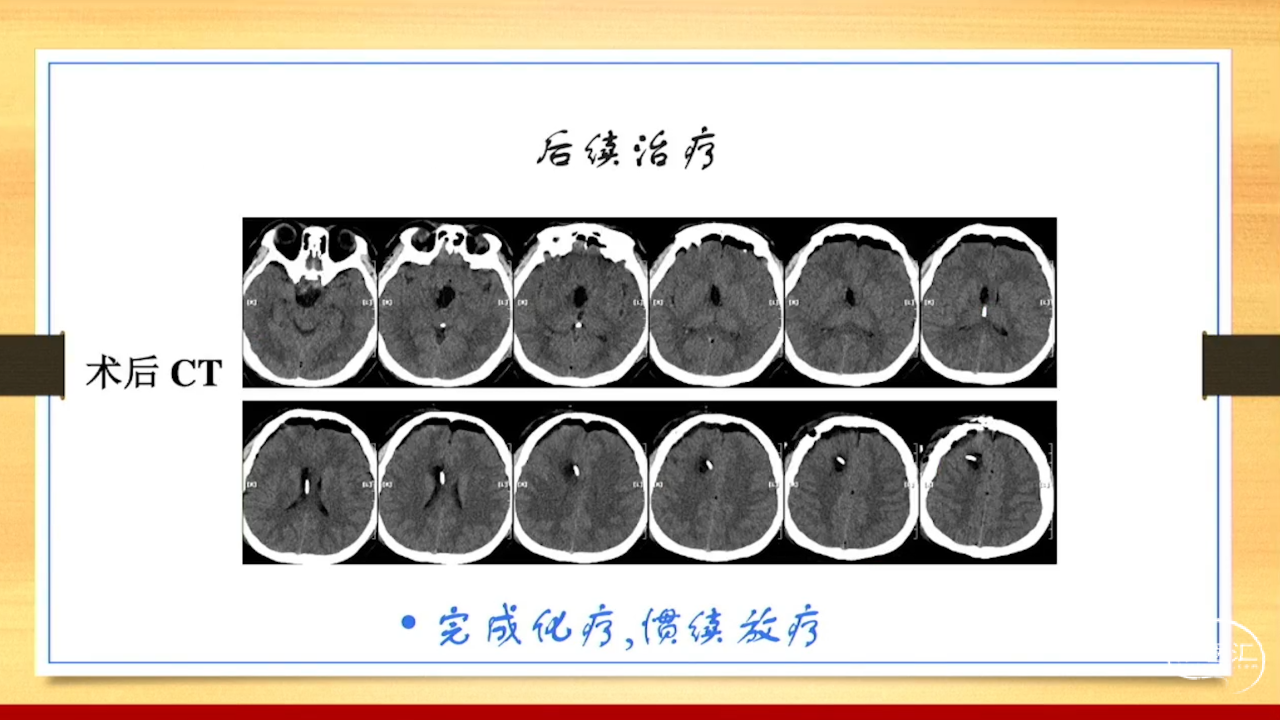

张荣教授:儿童颅内生殖细胞瘤的手术治疗

颅内生殖细胞肿瘤的治疗是手术、放疗、化疗、内分泌及其他多学科的整合治疗。及时、精准、合理的手术治疗是iGCT患者提高生存率、降低并发症、改善神经内分泌功能的关键。